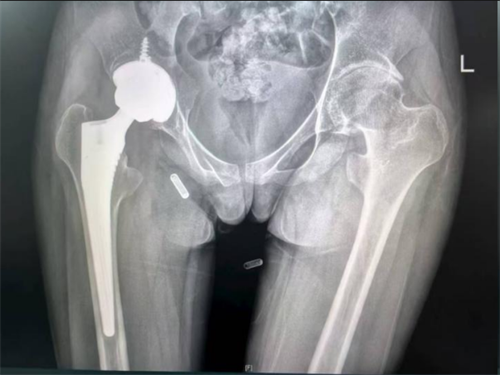

小雨进行右侧髋关节置换术后的X片

经过周密的术前准备,李良军主刀为小雨成功实施了右侧人工全髋关节置换术。术后三天,她在助行器辅助下重新下地行走。右侧髋部持续的剧痛消失了,她再一次感受到了“无痛行走”的喜悦。